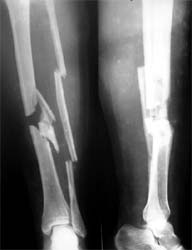

胫腓骨粉碎骨折 采用闭合穿钉法,带锁髓内钉内固定